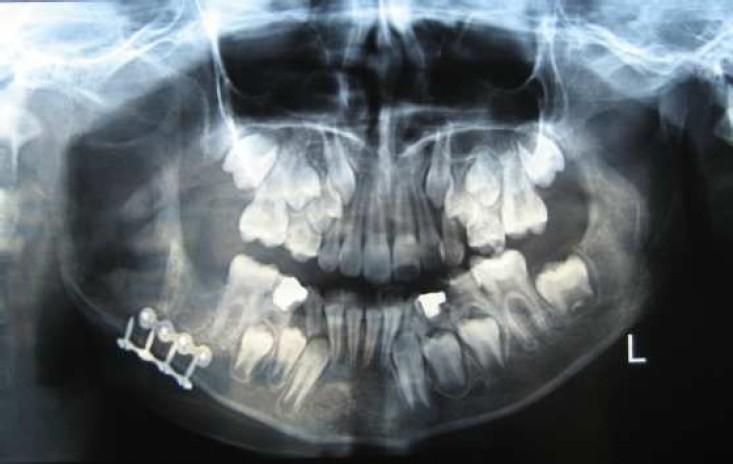

The neurilemmoma is a benign neoplasm of Schwann cell origin. One of the histopathologic subtypes of this tumor is ancient schwannoma which is characterized by degenerative alterations including cystic change, calcification, hemorrhage, and hyalinization.Intraosseous schwannomas especially ancient ones are rare tumors. Here we present a case of intraosseous ancient schwannoma in the lower jaw of an 11-year-old girl which caused a non-tender expansion. Radiographic examination showed a well-circumscribed, unilocular radiolucent lesion with thin sclerotic borders in the mandibular body and the ramus. Histopathologic examination of the incisional biopsy showed areas of typical Antoni A with verocay bodies and Antoni B that was strongly suggestive of a schwannoma. Complete excision of the lesion was done under general anesthesia. The histopathologic examination confirmed the primary diagnosis and also degenerative changes such as hyalinization and calcification. Based on these findings, the diagnosis of ancient schwannoma was made. No recurrence was observed in the follow-up examination after 3 months.

神经鞘瘤是一种起源于施万细胞的良性肿瘤。该肿瘤的组织病理学亚型之一是陈旧性神经鞘瘤,其特征为退行性改变,包括囊性变、钙化、出血和玻璃样变。骨内神经鞘瘤,尤其是陈旧性神经鞘瘤,是罕见的肿瘤。在此,我们报告一例发生于一名11岁女孩下颌骨的骨内陈旧性神经鞘瘤病例,该肿瘤导致无痛性膨隆。影像学检查显示下颌体和下颌支有一个边界清晰、单房性的透射性病变,边界有薄的硬化边。切开活检的组织病理学检查显示有典型的伴有Verocay小体的Antoni A区和Antoni B区,强烈提示为神经鞘瘤。在全身麻醉下对病变进行了完整切除。组织病理学检查证实了初步诊断,同时也发现了玻璃样变和钙化等退行性改变。基于这些发现,诊断为陈旧性神经鞘瘤。3个月后的随访检查未观察到复发。